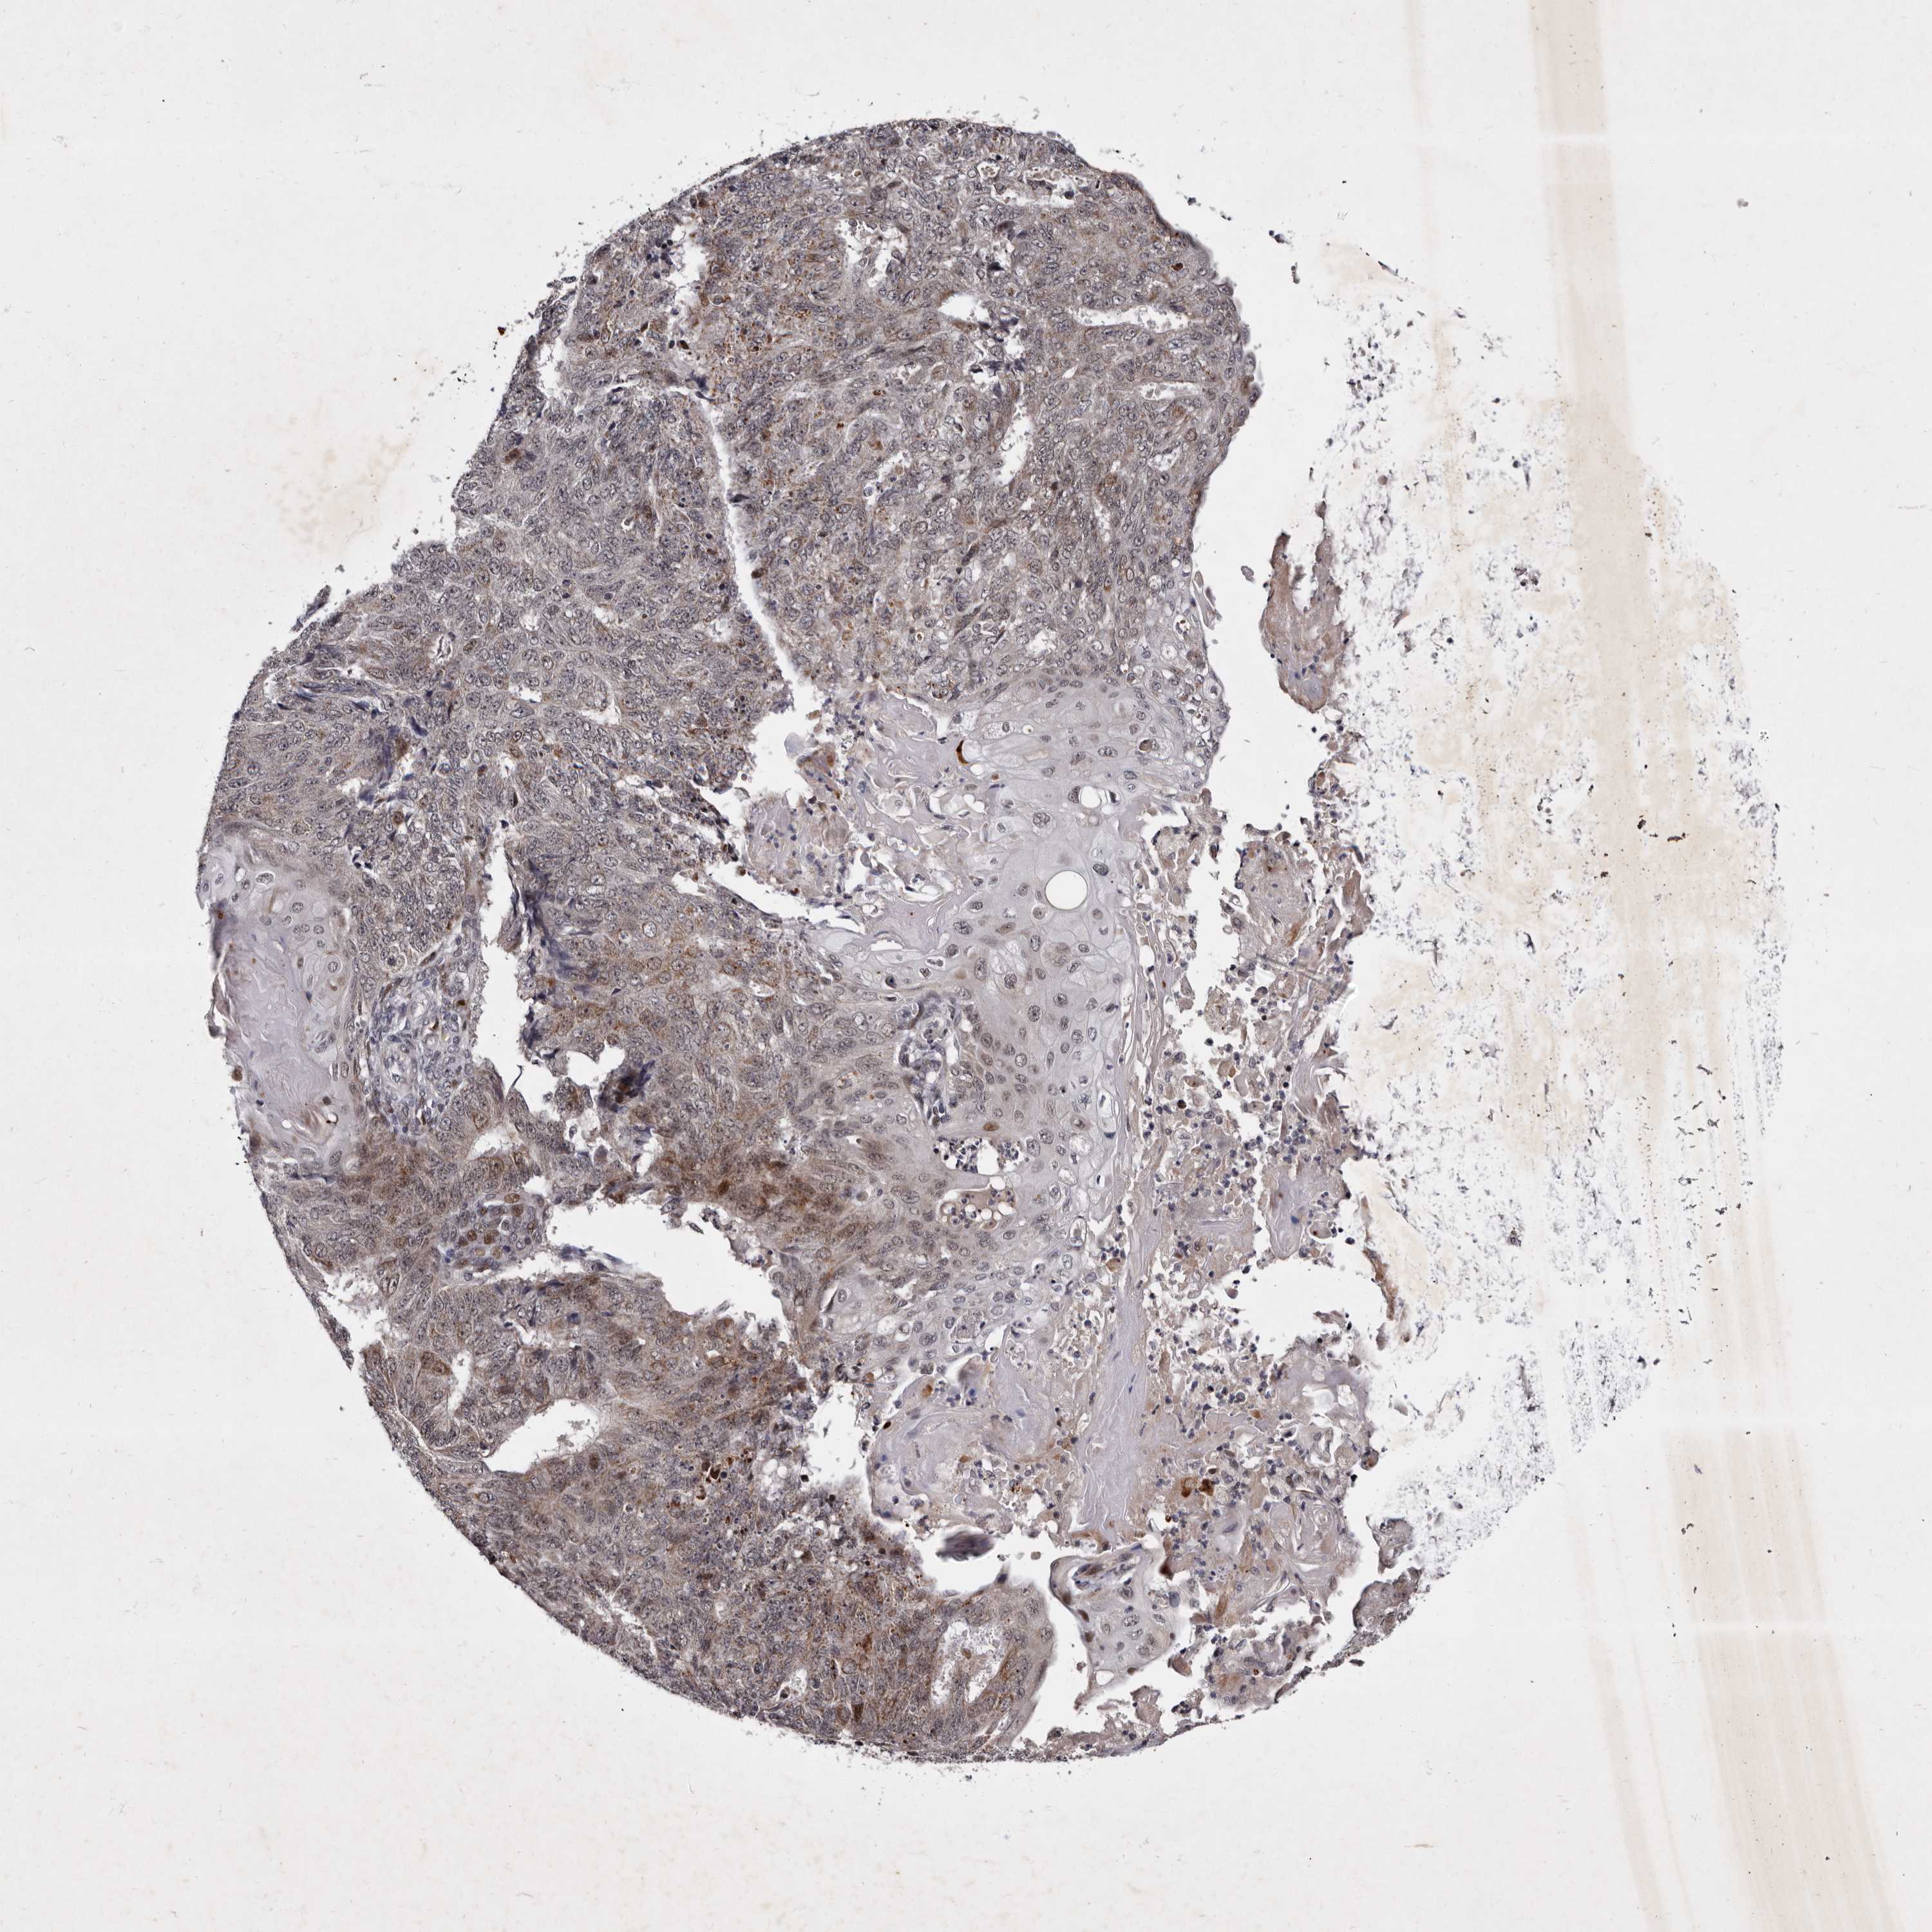

ENDOMETRIAL CANCER - Protein expressioni

A mouse-over function shows sample information and annotation data. Click on an image to view it in a full screen mode. Samples can be filtered based on level of antibody staining by selecting one or several of the following categories: high, medium, low and not detected. The assay and annotation is described here.

Note that samples used for immunohistochemistry by the Human Protein Atlas do not correspond to samples in the TCGA dataset.

Antibody stainingi

Antibody staining in the annotated cell types in the current human tissue is reported as not detected, low, medium, or high, based on conventional immunohistochemistry profiling in selected tissues. This score is based on the combination of the staining intensity and fraction of stained cells.

Each image is clickable and will lead to virtual microscopy that enables deeper exploration of all samples and also displays staining intensity scores, fraction scores and subcellular localization as well as patient and tissue information for each sample.

Antibody HPA025690

Staining

High

Medium

Low

Not detected

Intensity

Strong

Moderate

Weak

Negative

Quantity

>75%

75%-25%

<25%

None

Location

Nuclear

Cytoplasmic/membranous

Cytoplasmic/membranous,nuclear

Adenocarcinoma, NOS

Adenocarcinoma, metastatic, NOS